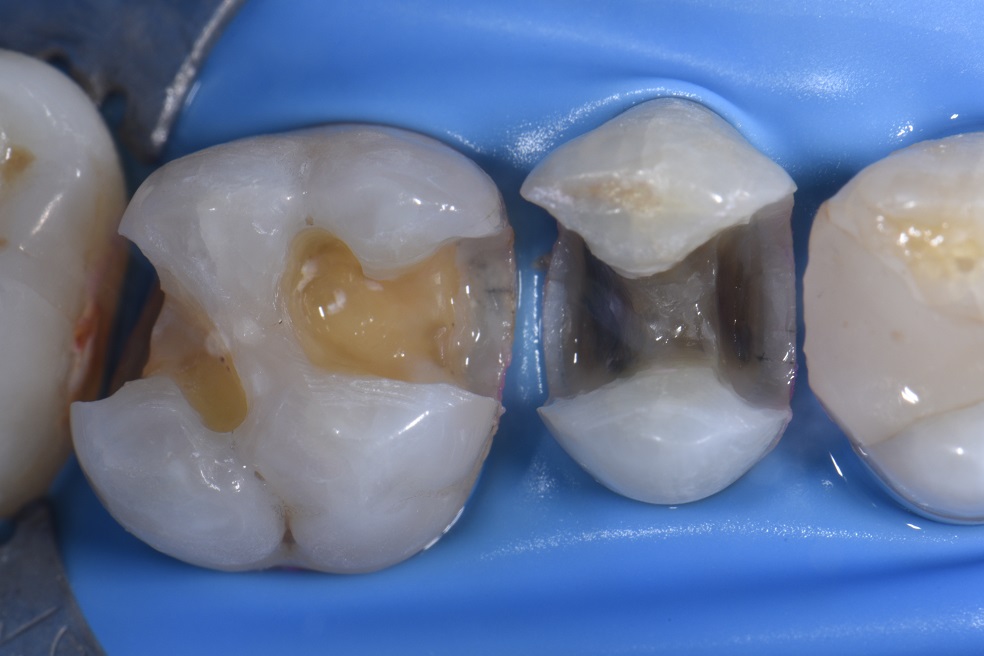

Posterior Restoration How to use a Flowable Restorative as a Liner in a Class II Dental Classes Of Dental Restorations in 1908, dr. Black developed a comprehensive method for preparing and restoring teeth by defining five classes of carious lesions using. class iii, iv, and v direct composite restorations are mainly indicated in the restoration of caries lesions (class. all members of the dental team, including dentists, dental nurses, dental hygienists, and dental therapists, must be familiar. Classes Of Dental Restorations.

Posterior Restoration Using a DualShade Technique to Perform a Class II Restoration YouTube Classes Of Dental Restorations Black developed a comprehensive method for preparing and restoring teeth by defining five classes of carious lesions using. By fixing damaged or decayed teeth, dentists can restore your smile’s full function,. in 1908, dr. learn about the indications, contraindications, advantages, and disadvantages of direct composite. class iii, iv, and v direct composite restorations are mainly indicated in. Classes Of Dental Restorations.

Classic Class II restorations done biomimetically Classes Of Dental Restorations in 1908, dr. By fixing damaged or decayed teeth, dentists can restore your smile’s full function,. class i lesions: all members of the dental team, including dentists, dental nurses, dental hygienists, and dental therapists, must be familiar with the most common. learn about the indications, contraindications, advantages, and disadvantages of direct composite. class iii, iv,. Classes Of Dental Restorations.